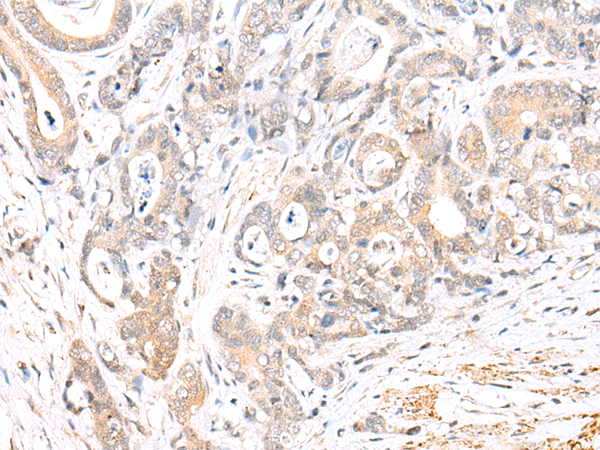

IHC positive control: |

Human thyroid cancer and human gastric cancer |

IHC Recommend dilution: |

25-100 |